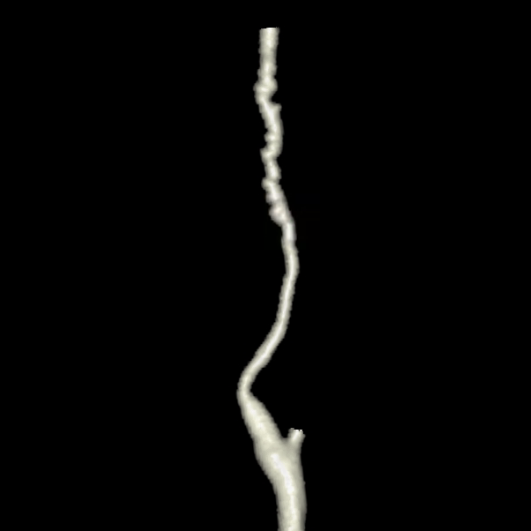

Бусы, о которых поговорим мы, найдены в шее одной из прекрасных пациенток, посетивших меня на КТ.